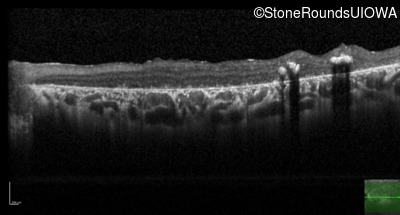

Optical Coherence Tomography - Right - 20/400 sc

Exemplar / OCT Stack